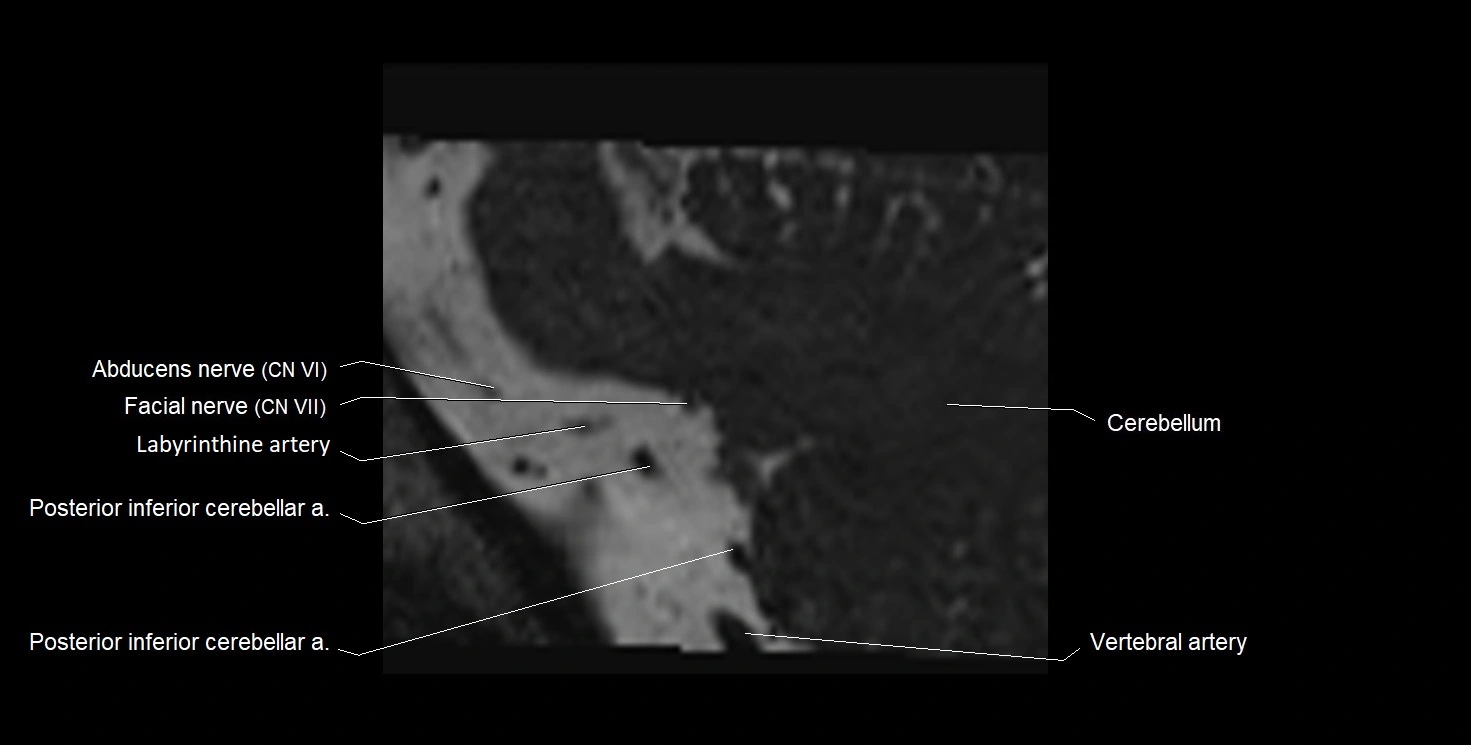

MRI Appearance

• The abducens nerve is a small, thin, linear structure

• Best visualized on high-resolution T2-weighted 3D MRI sequences (e.g., FIESTA or CISS)

• Seen as a hypointense (dark) line running from the brainstem at the pontomedullary junction, traversing the prepontine cistern, and entering Dorello’s canal under the petrosphenoidal ligament, then into the cavernous sinus, and finally the orbit

• May be challenging to visualize in standard MRI due to its small size

• Pathology may be inferred by absence, displacement, or enhancement of the nerve

MRI images

image